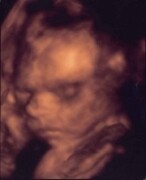

Ahojte, máte prosím někdo zkušenosti s tachykardií plodu? Zatím na každém CTG byly výkyvy. Nevíte, kolik je norma, popřípadě jestli to může nějak ohrozit mimčo?

Ahojky, norma je 130-160, já s tím mám taky problémy. U doktora nám to kolikrát vyskočí až na 200, odpoledne musím vždycky do nemocnice a tam už to máme kolem 140-150, takže nás pošlou zase domů.

Taky me tim strasili a mala je uplne v poradku. Takze bud v klidu. Norma je 120 - 180.

@Karusta Dole myslis jako tech 120? Nebo tu tvoji krivku kontrakci? Kontrakce nevim, tam asi nic neovlivnis. Ale bohuzel ti neporadim vic, nez jak jsme psala. Toto mi rekli tenkrat v porodnici, kdyz jsem to tez resila. Ze tech 120-180 je takovy prumer a normal. Ale pokud to je sem tam vic ci min, tak bych se tez nebala. Hlavne musi byt v klidu maminka a pak bude v poradku i miminko. Ja jsem jednou, kdyz to tam zacalo litat jako blazen (byla jsem tam sama) zacala zpivat male pisnicku, kterou jsem ji zpivavala vzdycky doma a svete div se, ona se uklidnila... Vnimaji kazdou \'\'nervozitu\'\' maminky, i kdyz si to my nepripoustime. Znaji nas lepe, nez bychom byly samy schopny uverit. Takze klid, usmev na tvari a uvidis, ze bude vsechno v poradku.Navic, kdyby se neco delo, doktori te jiste budou informovat!